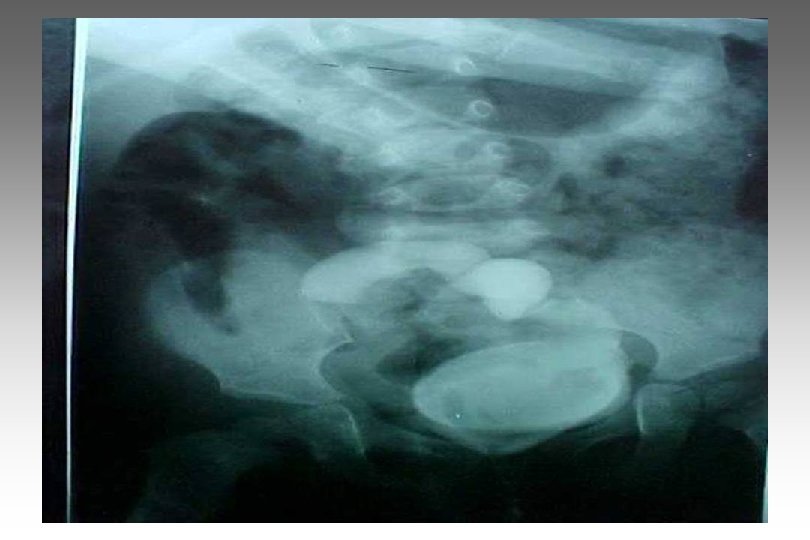

SECUENCIA DE IMAGEN o ECOGRAFIA. o CISTOURETROGRAFIA RETROGADA POST MICCIONAL. o PIELOGRAFIA ENDOVENOSA o GAMMAGRAFIA RENAL CON DMSA-TC 99. o RADIORENOGRAMA o UROGRAFIA POR RMN o TAC HELICOIDAL o ENDOSCOPIA VIRTUAL